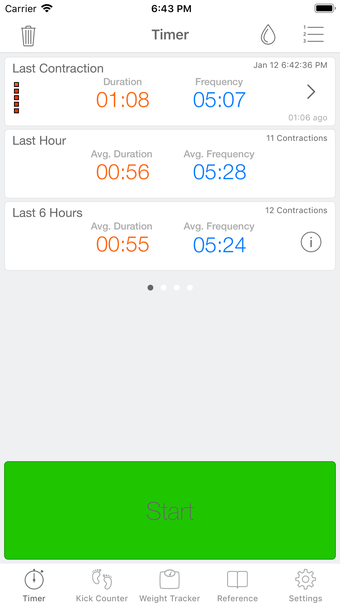

이 어플리케이션은 조기 분만을 겪는 여성들이 분만 과정을 지속적으로 추적할 필요가 있는 경우에 디자인되었습니다. 기능성을 희생하지 않고 사용자 친화적인 어플리케이션을 만들고자 했습니다.

이 어플리케이션은 분만 진행 상황을 명확하게 보여주며, 현재 분만 단계, 이전 및 현재 수축의 시작 및 종료 시간을 보여줍니다. Full Term은 수동으로 각 수축을 시작하고 중지할 필요가 없으며, 어플리케이션을 재시작하더라도 분만 기록을 추적합니다.